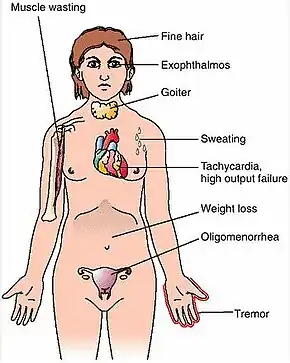

| Symptoms | Enlarged thyroid, irritability, muscle weakness, sleeping problems, fast heartbeat, weight loss, poor tolerance of heat,[1] anxiety, tremor of hands or fingers, warm and moist skin, increased perspiration, goiter, changes in menstrual cycle, easy bruising, erectile dysfunction, reduced libido, frequent bowel movements, bulging eyes (Graves' ophthalmopathy), thick red skin on shins or the top of foot (pretibial myxedema)[2] |

Graves' disease, also known as toxic diffuse goiter, is an autoimmune disease that affects the thyroid.[1] It frequently results in and is the most common cause of hyperthyroidism.[5] It also often results in an enlarged thyroid.[1] Signs and symptoms of hyperthyroidism may include irritability, muscle weakness, sleeping problems, a fast heartbeat, poor tolerance of heat, diarrhea and unintentional weight loss.[1] Other symptoms may include thickening of the skin on the shins, known as pretibial myxedema, and eye bulging, a condition caused by Graves' ophthalmopathy.[1] About 25 to 30% of people with the condition develop eye problems.[1][4]

The signs and symptoms of Graves' disease virtually all result from the direct and indirect effects of hyperthyroidism, with main exceptions being Graves' ophthalmopathy, goiter, and pretibial myxedema (which are caused by the autoimmune processes of the disease). Symptoms of the resultant hyperthyroidism are mainly insomnia, hand tremor, hyperactivity, hair loss, excessive sweating, oligomenorrhea, itching, heat intolerance, weight loss despite increased appetite, diarrhea, frequent defecation, palpitations, periodic partial muscle weakness or paralysis in those especially of Asian descent,[7] and skin warmth and moistness.[8] Further signs that may be seen on physical examination are most commonly a diffusely enlarged (usually symmetric), nontender thyroid, lid lag, excessive lacrimation due to Graves' ophthalmopathy, arrhythmias of the heart, such as sinus tachycardia, atrial fibrillation, and premature ventricular contractions, and hypertension.[8][9]